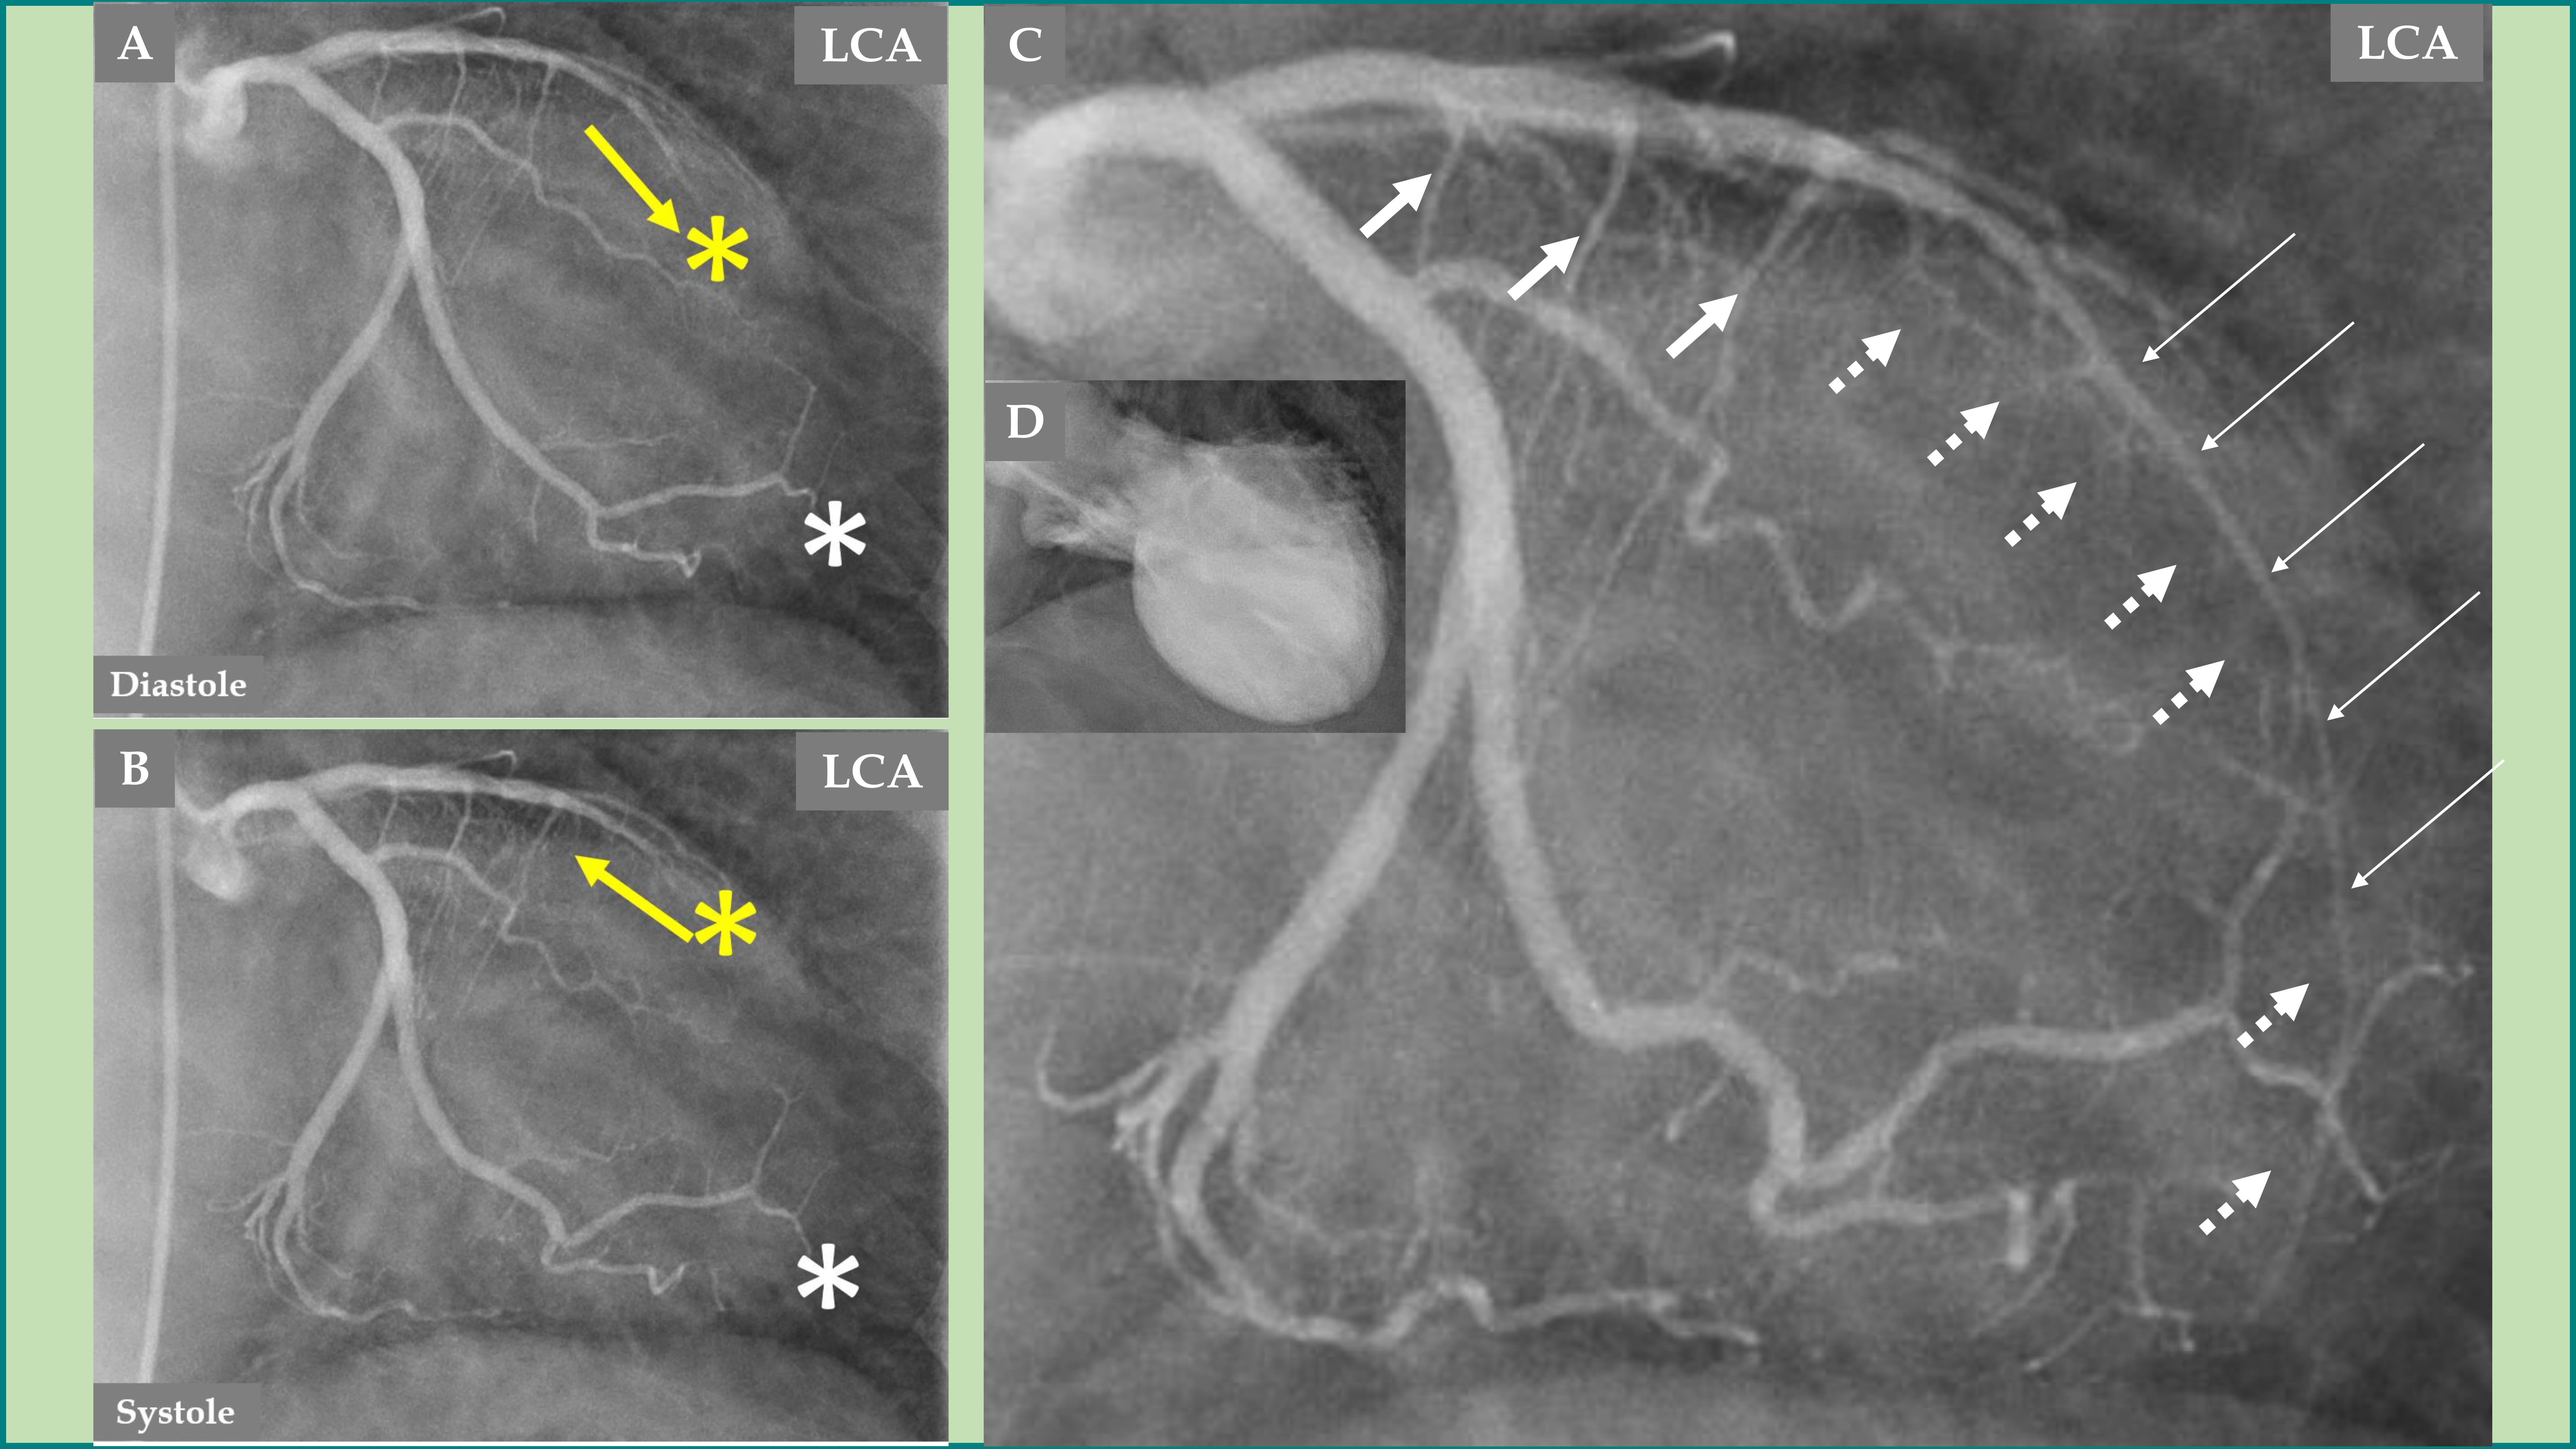

Fig. 4. Demonstration of remarkable changes in the LCA 5 months after the index presentation when the left ventricular dysfunction is completely normalized. LCA angiography during diastole (A). Contrast left ventriculography during diastole (B). LCA angiography during systole (C). Contrast left ventriculography during systole (D), which shows complete normalization of the left ventricular function. The LAD has a normal diameter, especially in the proximal two-thirds (A and C, thick white arrows), but mild systolic compression in the distal segment (C, thin white arrows). The septal branches from the distal half of the LAD are seen now during both diastole and systole (A and C, broken white arrows). The most remarkable change is the emergence of contrast in the left ventricle (yellow arrows during diastole in A and systole in C) due to reopening of the coronary artery–left ventricular micro-fistulae draining into the left ventricle.

During the follow-up 5 months later and with normalization of the LVWMA, all the above-mentioned changes in the septal branches, the LAD changes, and flow were normalized. Mild distal systolic LAD compression is seen most likely due to myocardial bridging (Fig. 4C).

An interesting finding, which forms a novel observation, is that no signs of CALVMF was observed during the index presentation with a mid-apical ballooning pattern of TS (Fig. 3C and Fig. 5A); however, during follow-up coronary angiography when the left ventricular dysfunction has completely normalized, there was clear signs of CALVMF, most probably arising from the distal marginal branches (Fig. 4A,C during diastole and systole and Fig. 5C). It is also clearly seen that the contrast staining moves to the left ventricular cavity during systole (Fig. 4C). These micro-fistulae were not visible during index presentation because of the compression by the myocardial stunning (myocardial cramp) caused by TS. The comparison between the index presentation, where there were no signs of CALVMF, and the follow-up 5 months later, where signs of CALVMF appeared clearly, is demonstrated in Fig. 5.